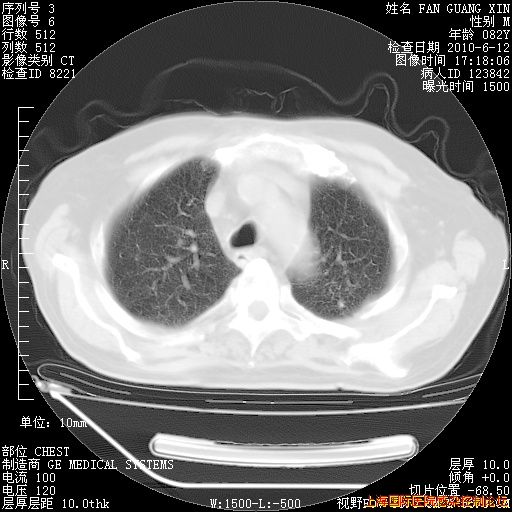

6月12日纵膈窗

整整相隔30天的肺部CT好像有所好转啊。甲强龙减量第3天,需要观察体温。

海管,自昨日你和我通完话后,不知您岳父消化道症状有无缓解?体温怎样?阅读7.12日胸部ct,个人认为目前激素治疗是有效的,甲强龙减量是适宜的。因在抗痨治疗,需密切观察肝功、肾功能和血常规。不过,老年、长期住院和大量使用激素,很担心菌群失调发生